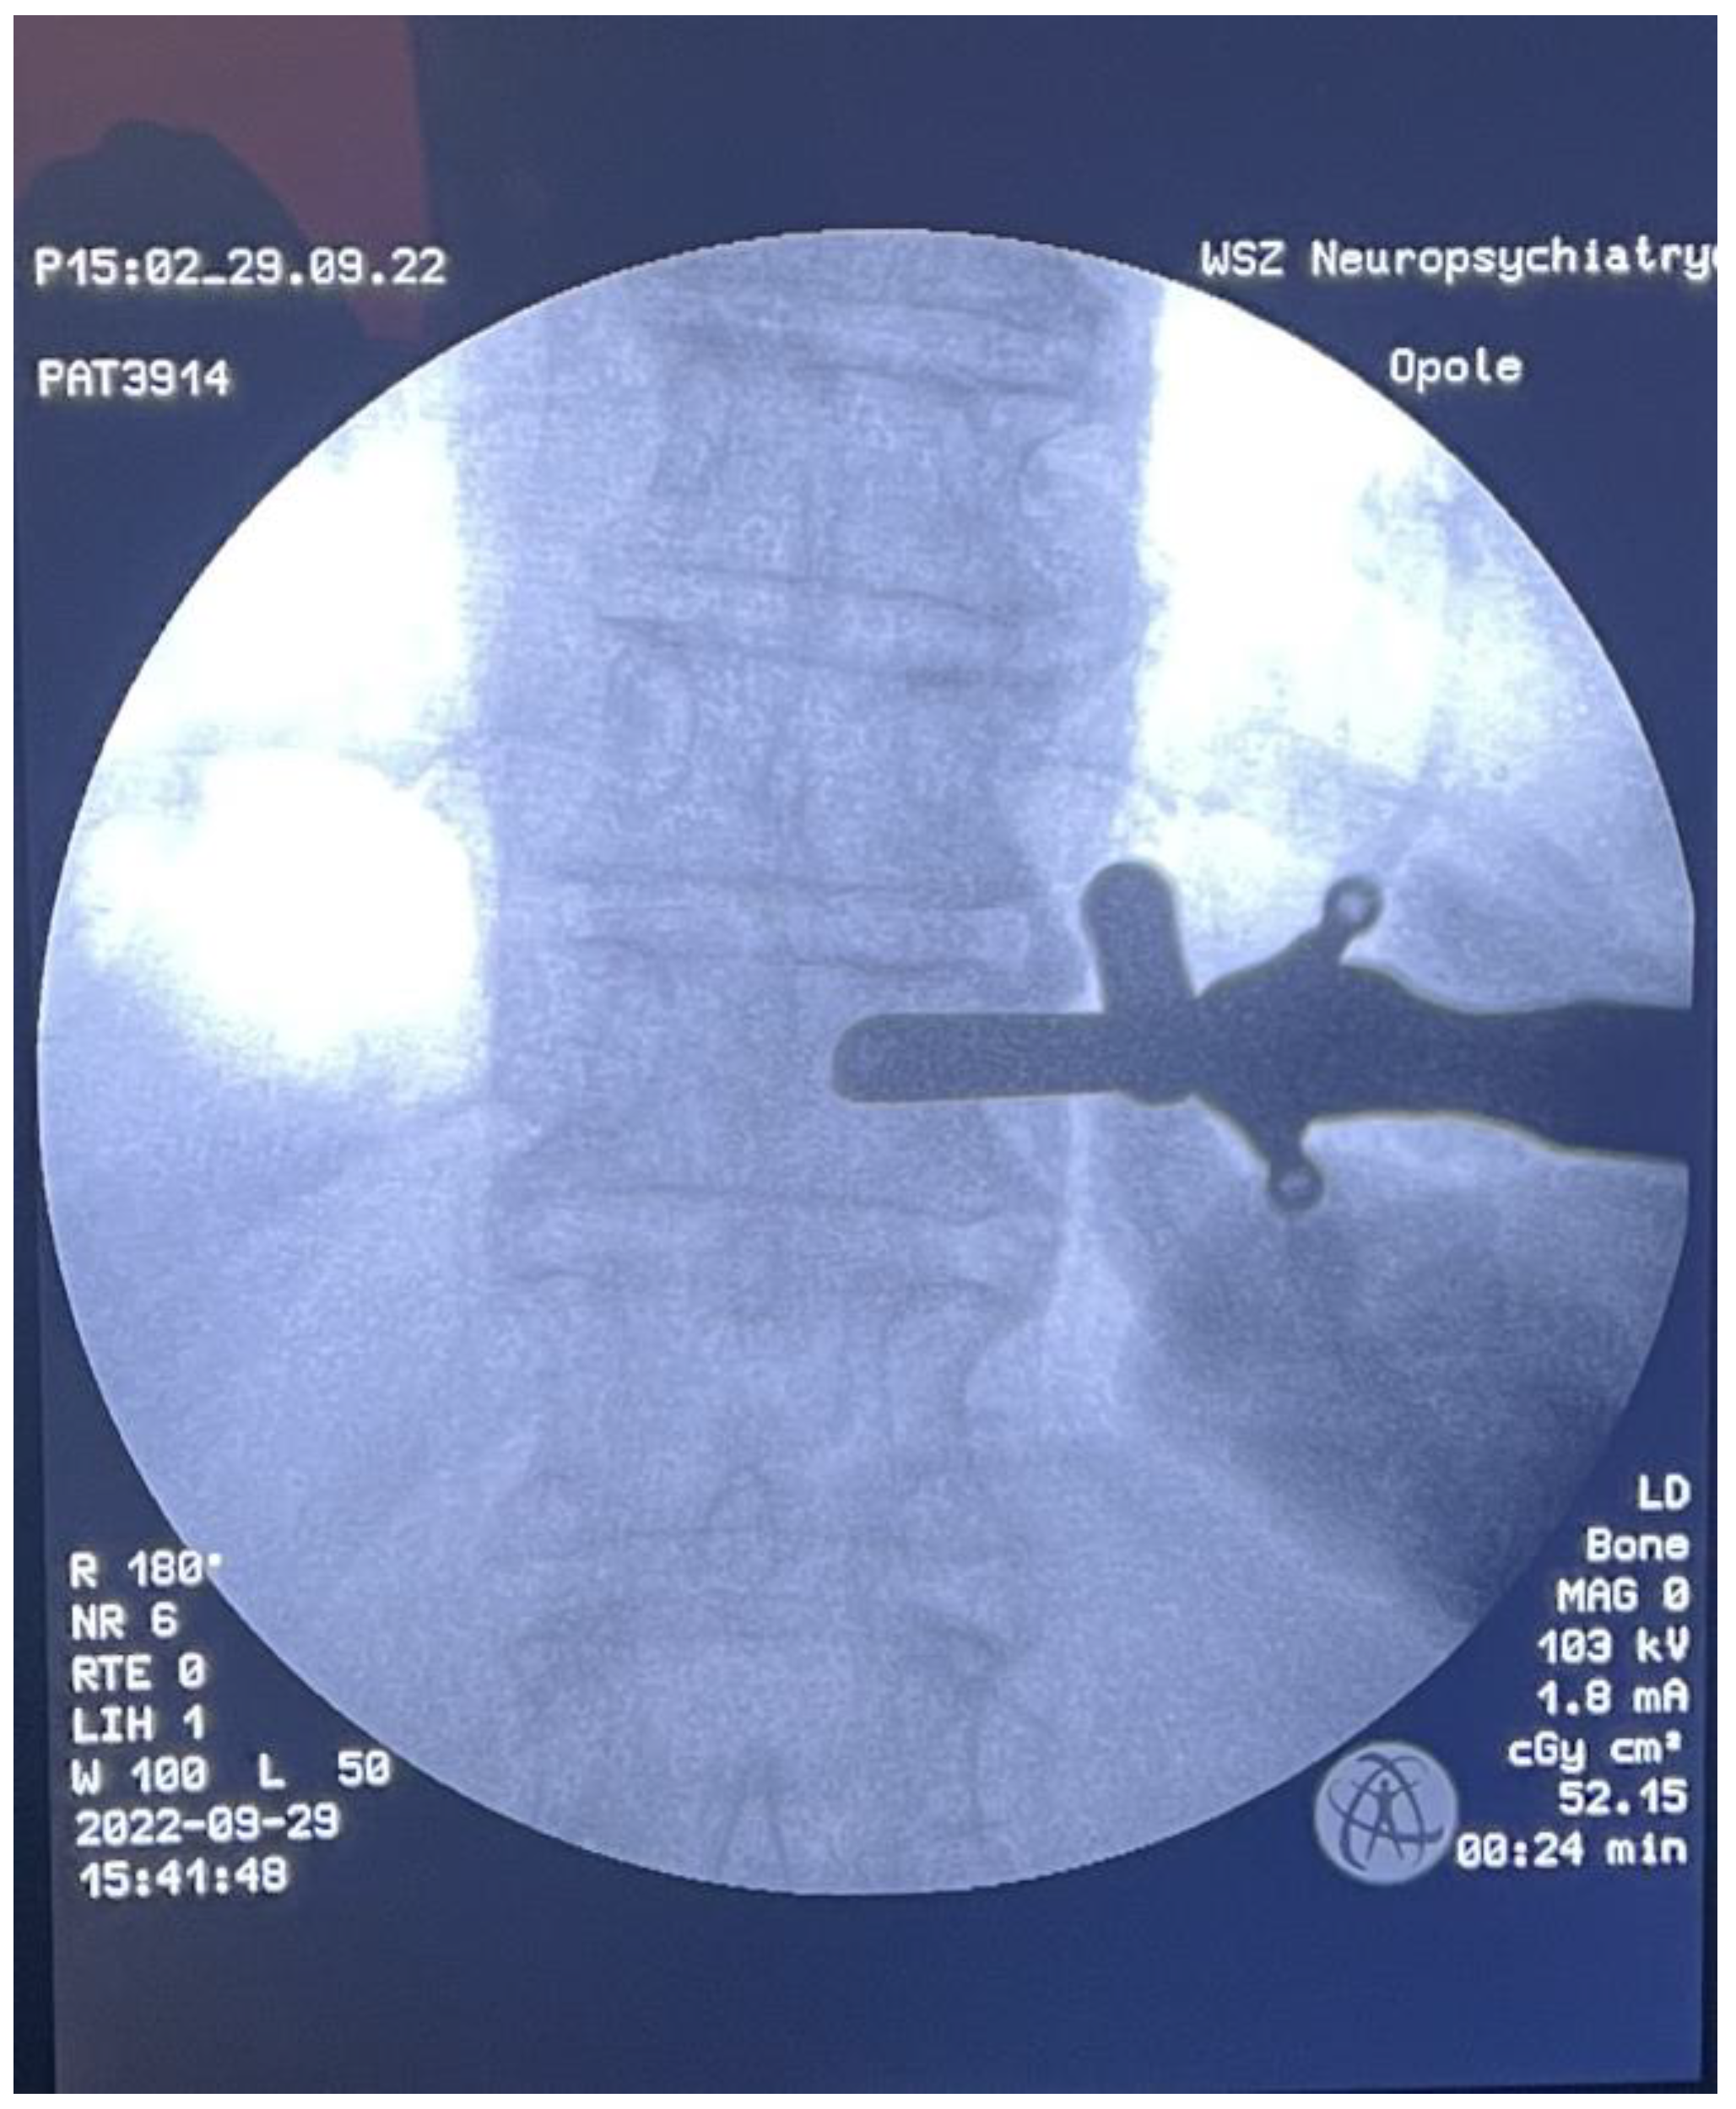

Fully Endoscopic Spine Separation Surgery in Metastatic Disease—Case Series, Technical Notes, and Preliminary Findings

3. Results